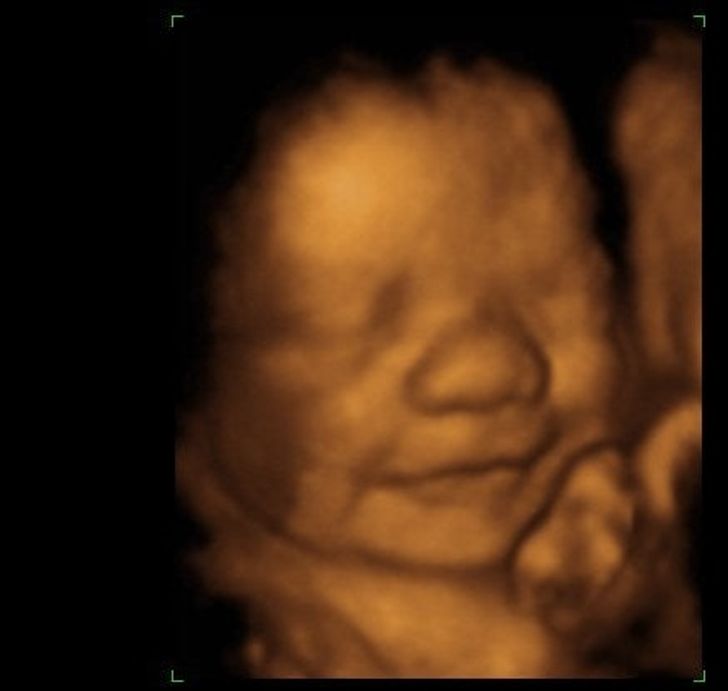

- Foshnjat buzรซqeshin edhe para se tรซ lindin.

Nรซse keni pasur fatin tรซ shihni fรซmijรซn tuaj duke buzรซqeshur nรซ ultratinguj, mos mendoni se po imagjinonit gjรซra qรซ nuk po ndodhnin. Njรซ studim qรซ shikoi mรซ shumรซ se 500 gra shtatzรซna duke pรซrdorur ultratinguj 4D, zbuloi se deri nรซ 31 fetuse nรซ tรซ vรซrtetรซ ishin duke buzรซqeshur. Tรซ gjithรซ buzรซqeshรซn pรซr njรซ kohรซ mesatare prej 3.21 sekondash secila.